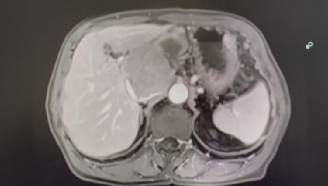

81岁的李阿伯因反复腹痛4个月,且病情持续加重后来金山医院就诊,经检查发现,李阿伯的肝脏尾状叶上长出一个8×6cm的肿物,患肝癌可能性大,突如其来的噩耗让整个家庭措手不及。

术前影像资料

肝脏肿瘤手术属于四级高难度手术,肝尾状叶肿瘤更因其位置较深、毗邻腹腔多个重要大血管、手术空间极为狭小而成为其中最困难、最复杂的一种,被认为是肝脏手术的“禁区”。